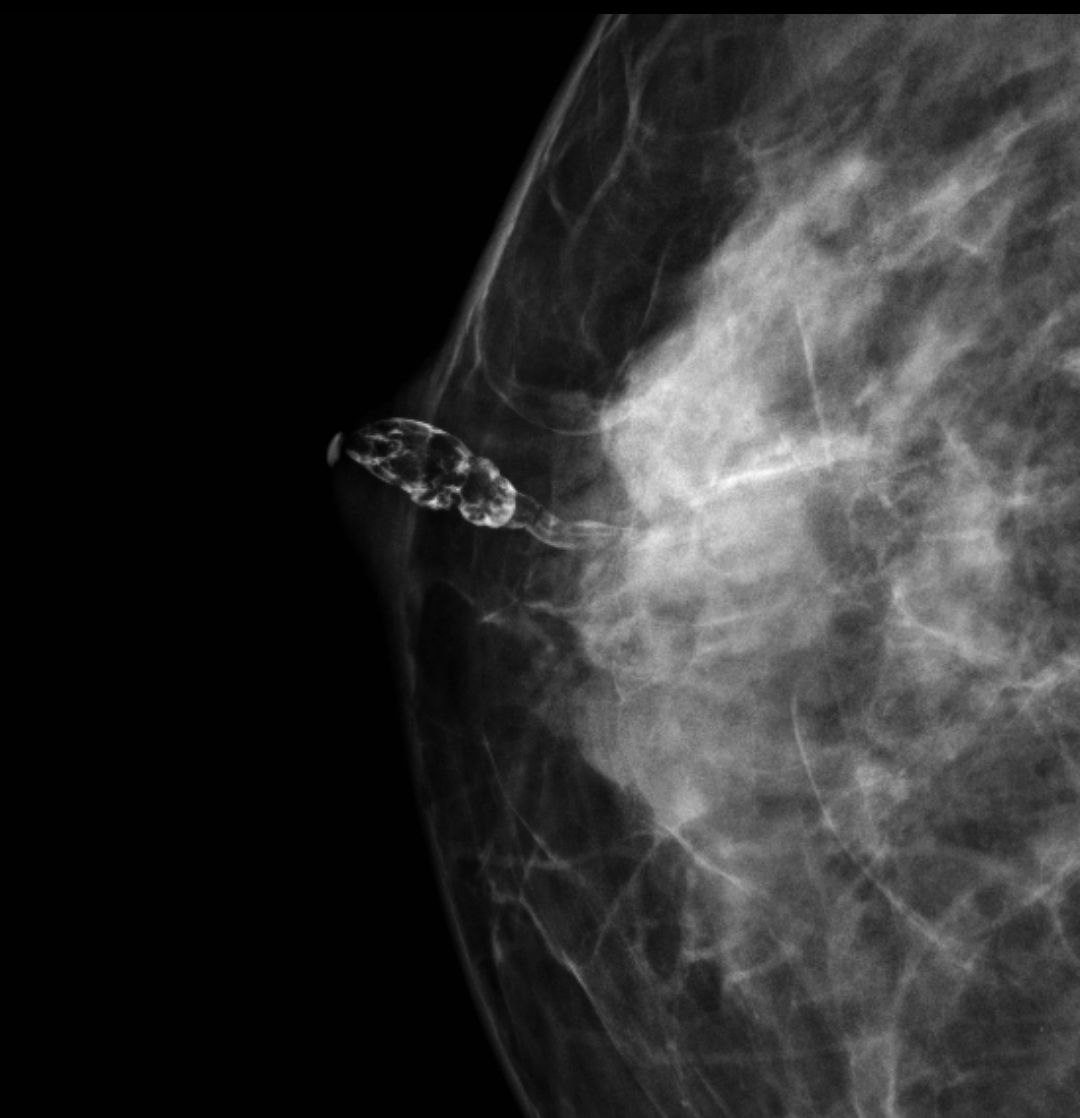

Дуктография молочной

Дуктография молочной 106 фотографий